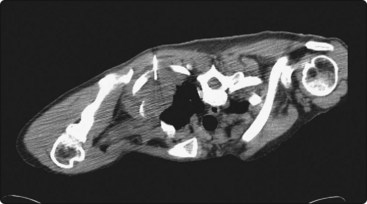

CT scanning

There are very few areas of the body which cannot be biopsied under CT control, and extremely small lesions can be sampled. Focal masses of several millimeters within the lung and skull base (Fig. 3.2) can be biopsied and retroperitoneal biopsies are limited only by availability of needles long enough to traverse the abdomen of large patients. Traversing with fine needles offers fewer risks compared with the larger-caliber needles.7 CT gantry tilt also further facilitates lesion access where appropriate.

image image

Fig. 3.2 (A) Circular low dense lesion right retropharyngeal node in a patient post right parotidectomy and radiotherapy for parotid squamous cell carcinoma. (B) Coaxial fine needle aspiration biopsy technique under CT control confirmed nodal recurrence. The utility of CT biopsy techniques and fine needle aspiration biopsy helped direct this patient’s management.

Localization of the needle tip within a lesion is very accurate with CT (Fig. 3.3). It provides detailed cross-sectional images of the body which are not limited by the same physical properties as are ultrasound images, such as interference from bowel gas and bone.